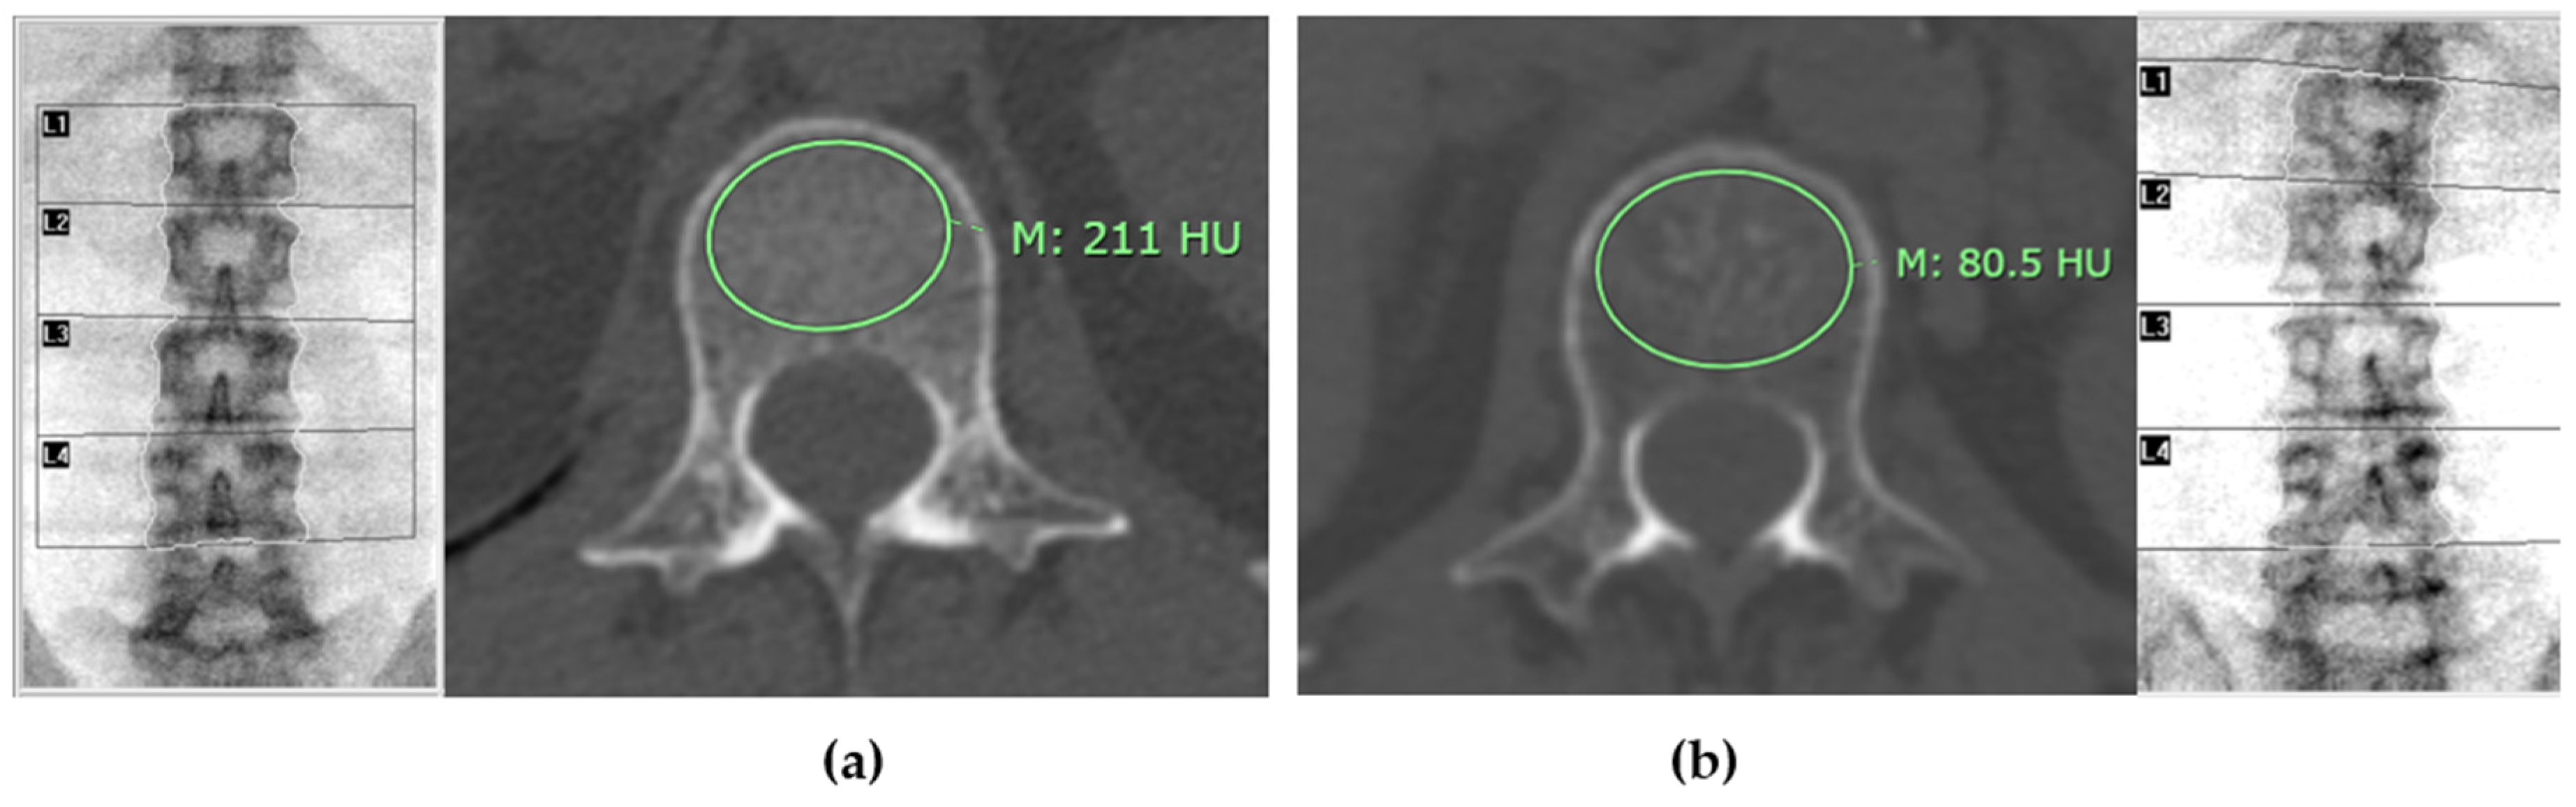

CT attenuation values for each L1-L4 vertebrae were measured on axial images from non-contrast CT scans, using bone window setting. The measurement was performed at the midpoint of each vertebra’s height, with the Region of Interest (ROI) placed specifically on the trabecular bone. The ROI was drawn as large as possible, avoiding areas with artifacts, degenerative changes, bone islands, or hemangioma, as shown in Figure 1. The results are reported in Hounsfield units (HU) [11].

Figure 4 illustrates distinct differences in mean CT attenuation values of patients in different groups: panel (a) depicts a patient classified in the normal bone mass group, while panel (b) shows a patient in the osteoporosis group.

Figure 1. The method for measuring CT attenuation values in cross-sectional images involves placing the region of interest (ROI) specifically on the trabecular bone area. In this approach, M represents the mean CT attenuation value.

Figure 4. Mean CT attenuation of patients in different groups. Panel (a) illustrates a patient classified in the normal bone mass group based on the lowest T-score from DXA, exhibiting a mean CT attenuation of approximately 211 Hounsfield Units (HU). In contrast, panel (b) depicts a patient in the osteoporosis group, characterized by a significantly lower mean CT attenuation of 80.5 HU. This comparison underscores the distinct differences in bone density as measured by CT attenuation values across these classifications.